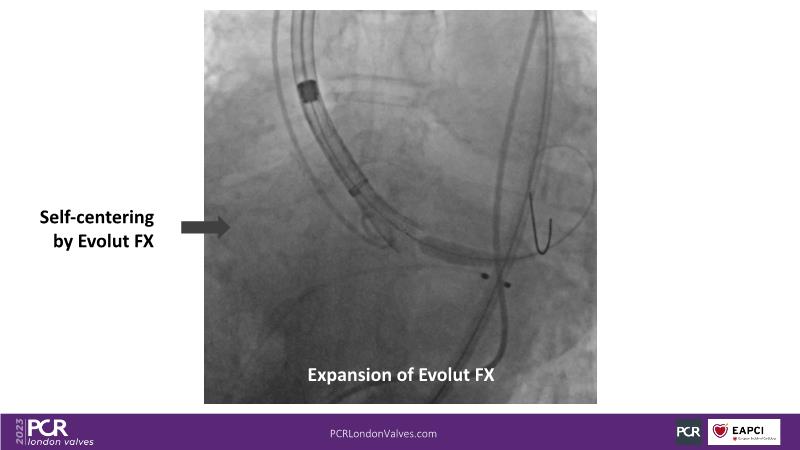

Defying complexity: achieving optimal TAVI procedural outcomes in challenging anatomies with the new Evolut FX

Watch this session to understand factors to consider when deciding on valve selection, recognize the significance of device choice and implantation technique in redo-TAVI, and acquire insights into anticipating challenges associated with implanting a bicuspid valve, large anatomy, and a horizontal aorta.

- To learn how to anticipate the challenges of implanting a bicuspid valve, large anatomy, horizontal aorta